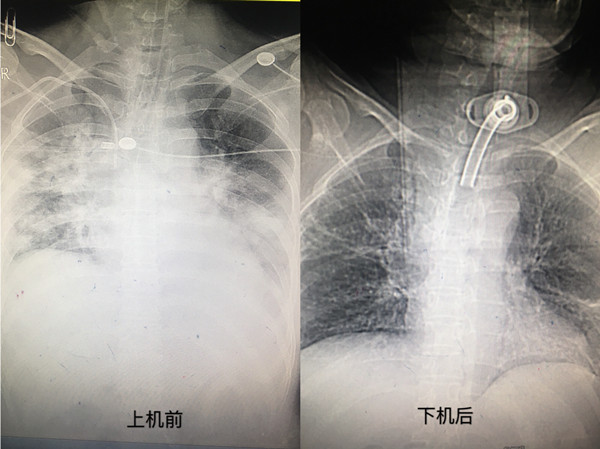

3月14日慕名而来的赵某因“重症肺炎”转入我科,入院时在机械通气下仍存在严重缺氧,呈昏迷状。危急关头,急诊科裴红红教授带领下的ECMO团队立即进行了病情评估,决定应用ECMO辅助患者呼吸功能;随即,整个团队有条不紊地开展启动置管、预充等工作,整个过程分工明确、动作娴熟、配合默契。当仪器运转后患者体内引出的暗红色的静脉血,立即变成鲜红的富氧血再次回输到患者体内,患者的血氧饱和度也逐步上升到90%以上……。经过ECMO团队的精心治疗与细心护理,患者肺部情况逐渐好转,1周后逐渐下调ECMO支持力度并成功脱机。当患者成功下机的那一刻,家属与患者都流下了激动的泪水。出院时,患者家属特意找到裴主任,感激的说 “如果不是ECMO,不是医护人员这么多天的悉心照料,我的亲人可能已经无法站在这里,千言万语都无法表达我们一家人对医护人员的感谢”,并送上锦旗表达对救命之恩的感谢之情。